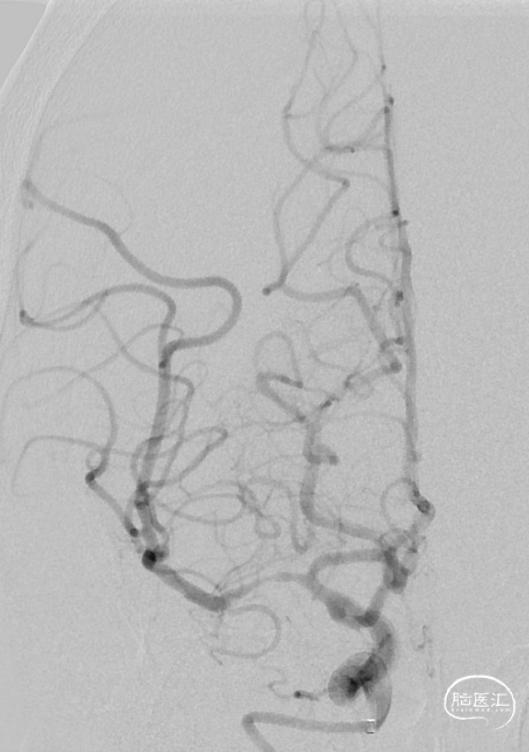

造影显示RICA:C1段起始部闭塞,残端呈锥形,TICI分级0级;RMCA未显影,远端由RACA经皮层支少量代偿,ASITN分级1-2级。

复查造影见支架展开良好,支架内及远端血流通畅,TICI分级3级。术顺,术毕,Proglide缝合术口。